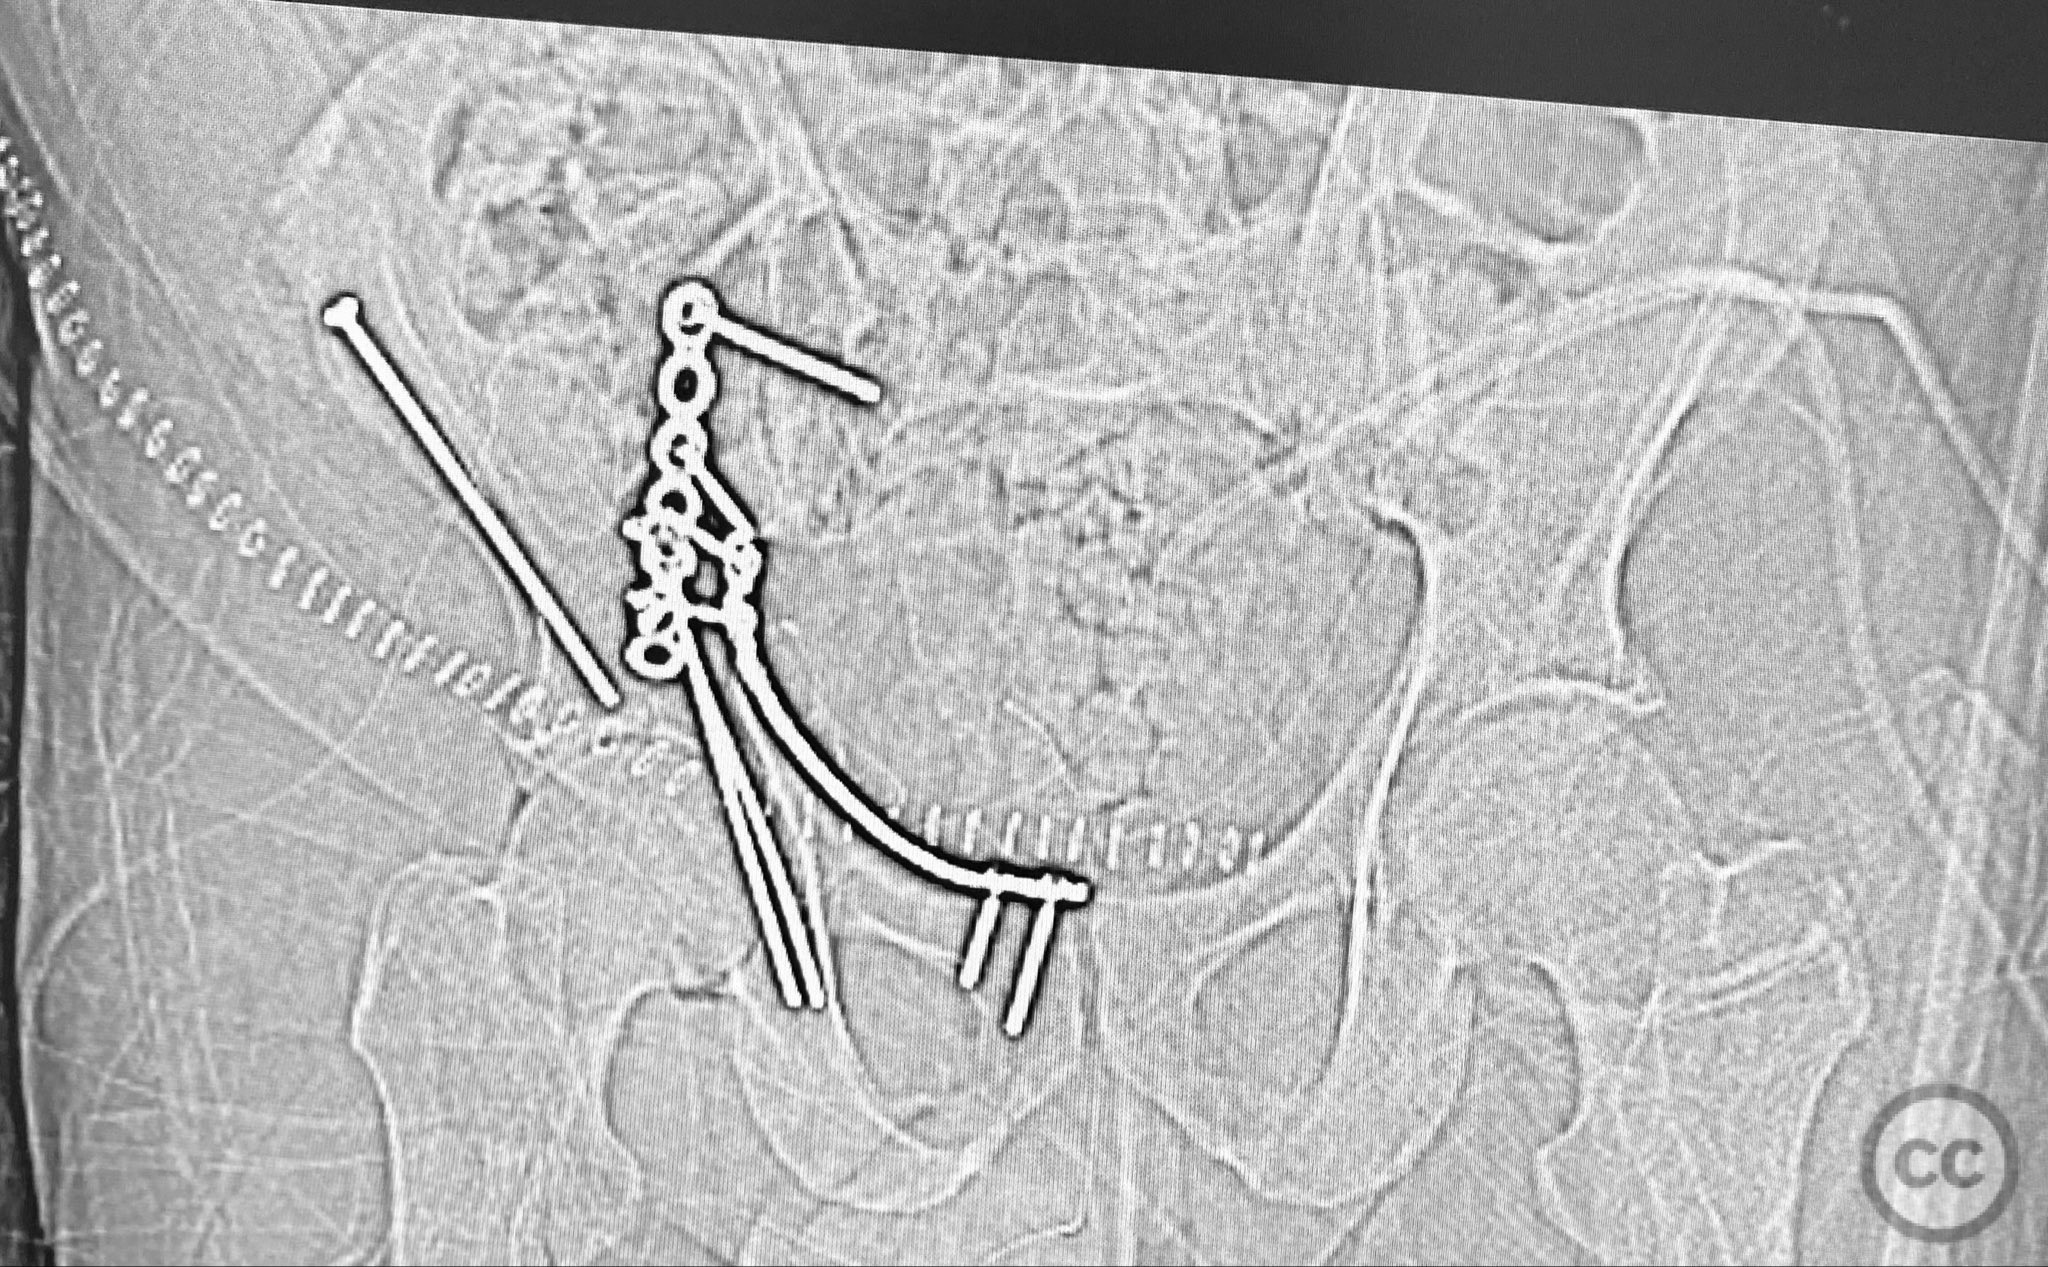

Clinical and radiological findings:  A patient presented with a combined anterior column and posterior hemi-transverse (AC/PHTr) acetabular fracture. Plain radiographs demonstrated multiple displaced fragments involving the acetabular dome and femoral head region, with clear disruption of the anterior column and posterior transverse components. Advanced imaging, including axial and coronal CT, provided detailed visualization of cortical surface displacement, fragment orientation, and associated soft tissue status. The edge of the intact dome and femoral head injuries were identified, as well as a residual defect at the edge of the dome following reduction. AO/OTA classification: 62B2 (anterior column with posterior hemitransverse).

Planning remarks:  The preoperative plan was to utilize an ilioinguinal approach, specifically employing the iliac, middle, and intrapelvic intervals for exposure. The plan included anatomical reduction of the anterior column and posterior hemi-transverse fragments using bone clamps, followed by stabilization with buttressing plates and interfragmentary lag screws. No intraoperative traction was planned.